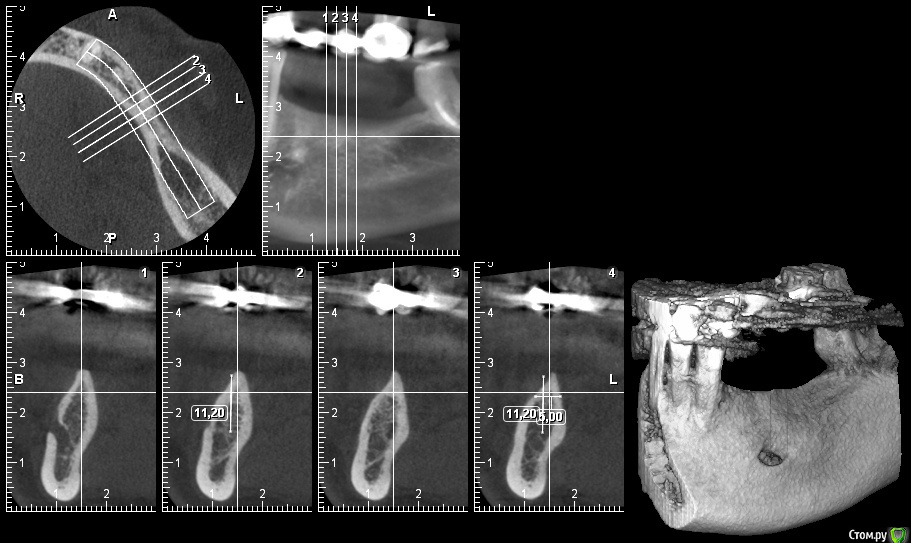

gum Опубликовано 30 июля, 2015 Поделиться Опубликовано 30 июля, 2015 Всем привет. Нужен совет: 1. Как поведет себя имплантат альфа био 8,0*4,2 при высоте коронки 1,2-1,3. по месту 36 зуба 2. По данному КТ планировал по месту 34: 3,75*10,0, 35,36,37: 3,75*8,0 + НКР, Блоки еще не делал, и пациентка не хочет , боится. (при протезировании коронки планирую сделать вместе, тк высота коронок превышает длину имплантов).Есть ли смысл идти таким путем, или блоки и попытаться увеличить толщину и высоту гребня. Ссылка на комментарий

Доктор Добрых Дел Опубликовано 30 июля, 2015 Поделиться Опубликовано 30 июля, 2015 Всем привет. Нужен совет: 1. Как поведет себя имплантат альфа био 8,0*4,2 при высоте коронки 1,2-1,3. по месту 36 зуба 2. По данному КТ планировал по месту 34: 3,75*10,0, 35,36,37: 3,75*8,0 + НКР, 12.jpgВ область 35 не ставил бы имплантат.34-36,37 за глаза. Ссылка на комментарий